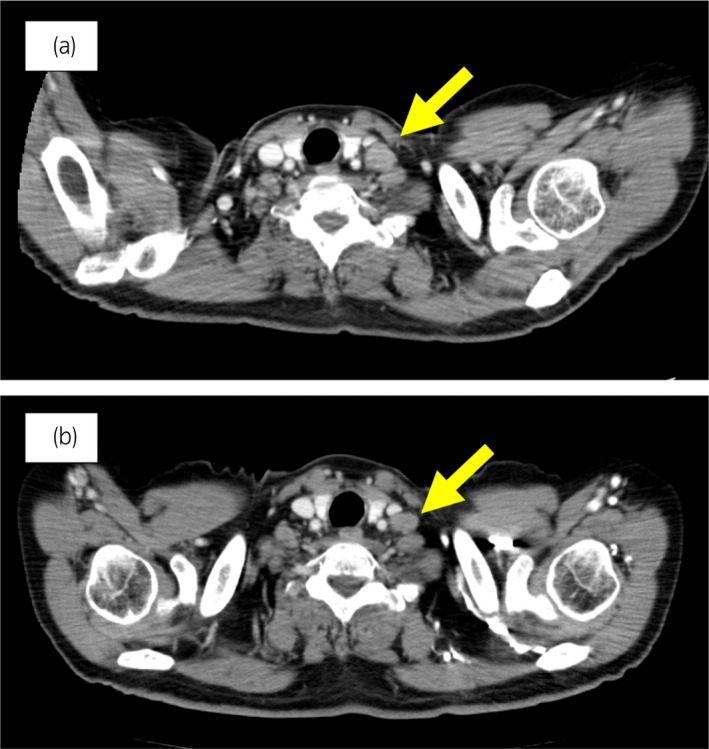

70 歲男性被診斷為轉(zhuǎn)移性 PC,cT3bN1M1b,Gleason 評分(GS)為 4 + 5 = 9,前列腺特異性抗原(PSA)水平為 40.8ng/ml,3 年前伴有胸椎轉(zhuǎn)移。 對前列腺進(jìn)行聯(lián)合雄激素阻斷 (CAB) 治療和質(zhì)子放射治療 (78.0Gy/39fr)。 PSA 水平降至 <0.01ng/ml,CAB 在 2.5 年后停止。 停止 CAB 五個(gè)月后,他出現(xiàn)背痛,PSA <0.01 ng/ml。 計(jì)算機(jī)斷層掃描 (CT) 掃描檢測到多處肝、骨和淋巴結(jié)轉(zhuǎn)移,神經(jīng)元特異性烯醇化酶 (NSE) 水平高達(dá) 171ng/ml(圖 1a)。 骨轉(zhuǎn)移活檢顯示神經(jīng)內(nèi)分泌前列腺癌 (NEPC) 的診斷(圖 2),患者被轉(zhuǎn)診至佳學(xué)基因合作醫(yī)院。 內(nèi)分泌腫瘤正確治療醫(yī)生用順鉑、依托泊苷和亮丙瑞林治療。 第三個(gè)療程后,轉(zhuǎn)移部位明顯縮?。▓D 1b)。 順鉑和依托泊苷治療 1 年,但患者因神經(jīng)病變要求停藥。 他開始服用恩雜魯胺。 治療 3 個(gè)月后,患者出現(xiàn)背痛和左鎖骨下淋巴結(jié)腫大(圖 3a)。 肝轉(zhuǎn)移保持不變,順鉑治療后縮小。 通過腫瘤正確用藥850基因檢測證實(shí)了 BRCA2 突變。根據(jù)基因檢測結(jié)果,主治腫瘤科醫(yī)生給予了奧拉帕尼。 三個(gè)月后,背痛好轉(zhuǎn),淋巴結(jié)轉(zhuǎn)移縮小,確定為部分緩解(PR)(圖3b)。 肝轉(zhuǎn)移灶保持不變。

圖 3:案例 1. 開始使用奧拉帕尼之前和之后 3個(gè)月的鎖骨下淋巴結(jié)轉(zhuǎn)移的 CT 圖像。 (a) 治療前和 (b) 奧拉帕尼治療后 3 個(gè)月。 黃色箭頭顯示轉(zhuǎn)移淋巴結(jié)。